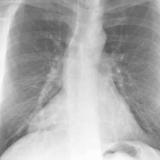

Case 4a

Peric effusion

Date: 03/17/2004

Views: 2989